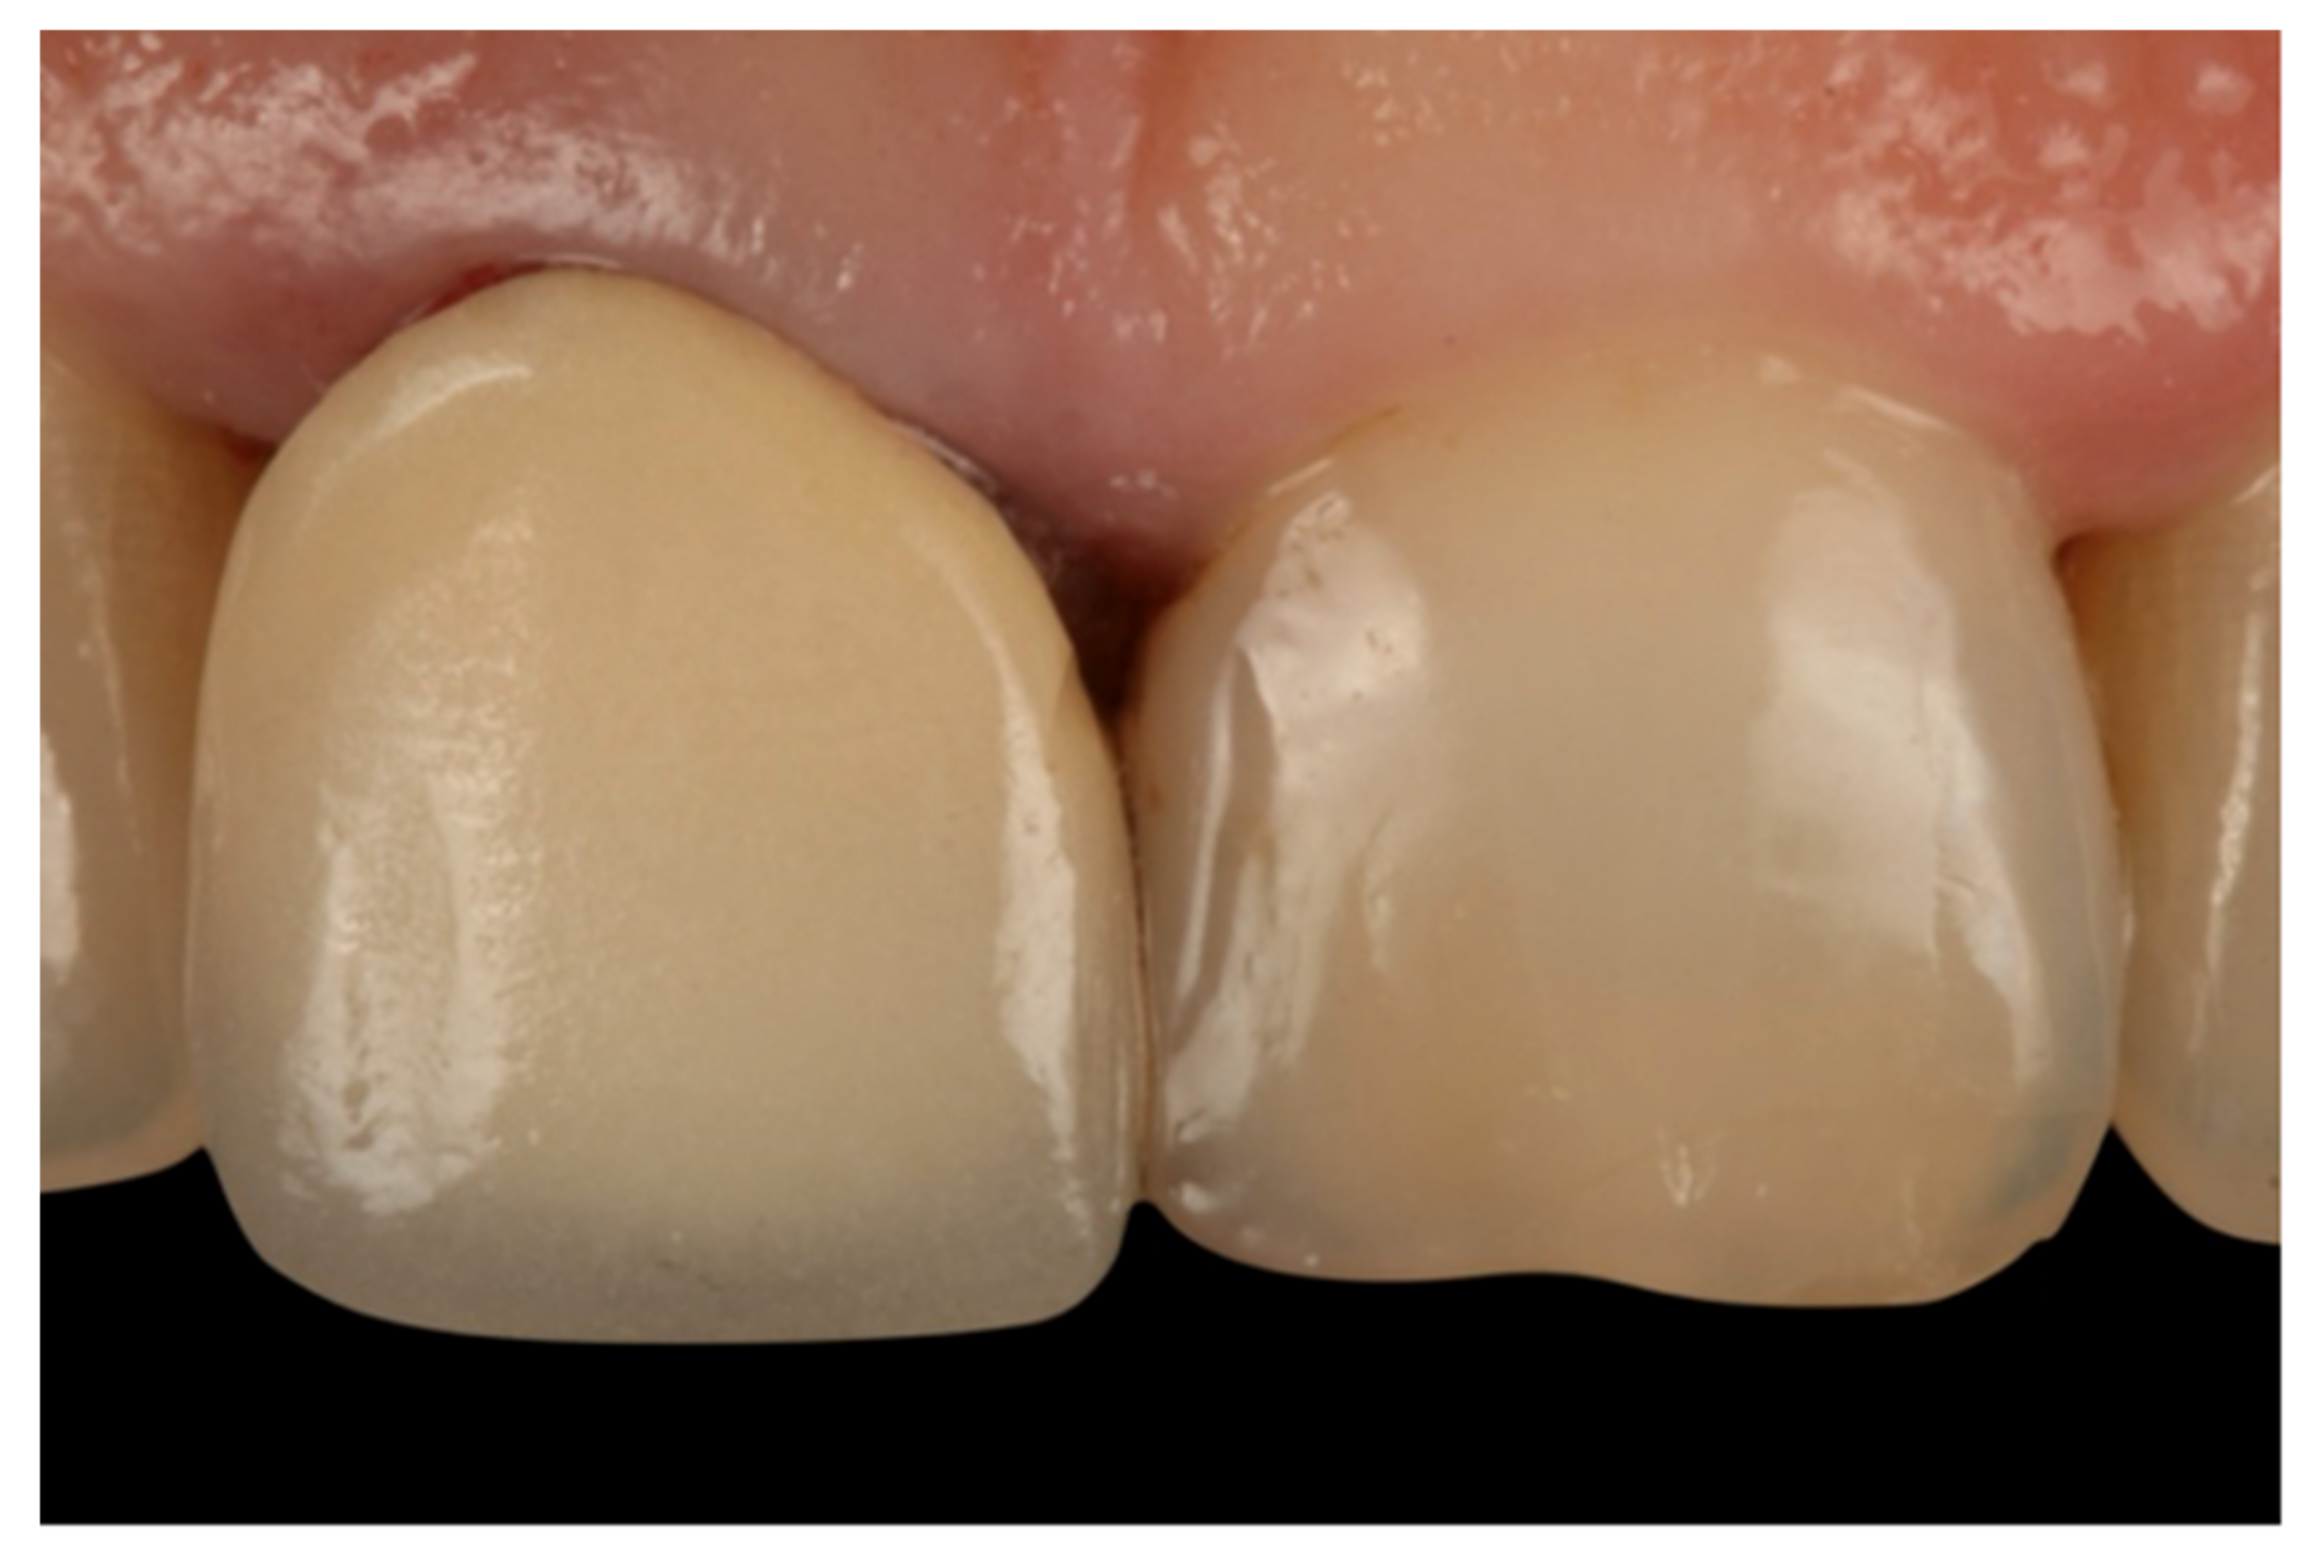

- Teeth treated with this technique presented improved plaque indices, stable probing depths, increased gingival thickness, and stable gingival margins over the 6-year follow-up.

- Treatment with a fixed prosthesis using the BOPT technique has a positive impact on patient satisfaction, especially in cases concerning the re-treatment of old fixed prostheses. This fact is due to the esthetic improvement not only of the restoration but also of the surrounding tissues, as it improves gingival quality by thickening the tissue, thus preventing gingival recession.